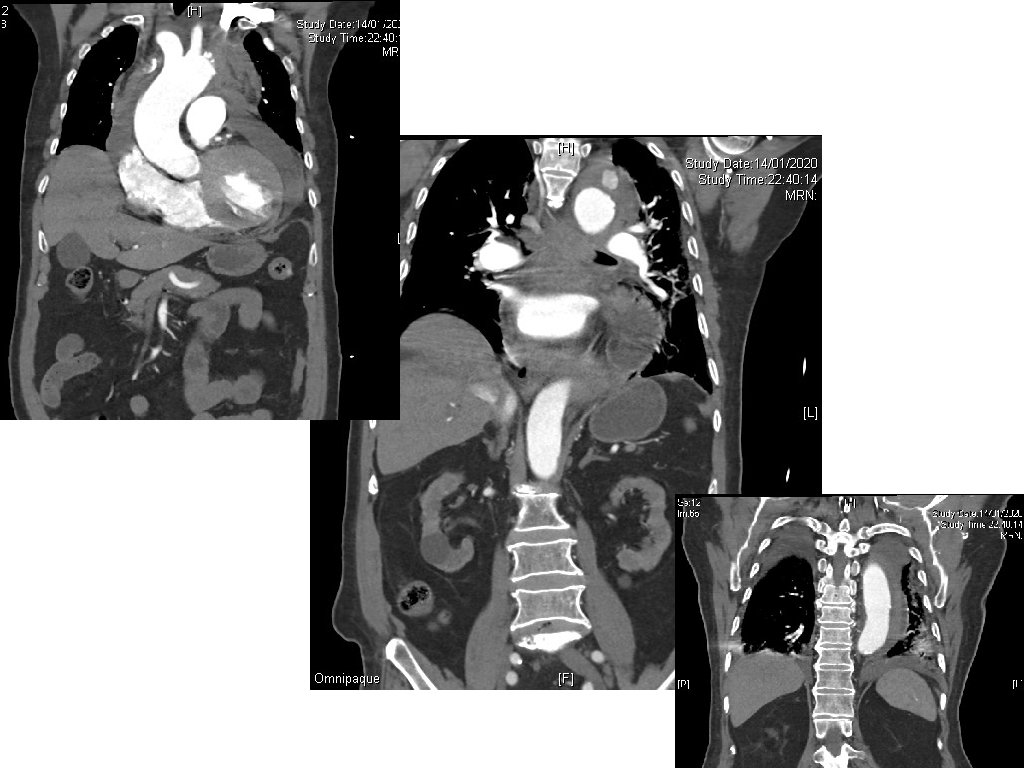

Case 3 • A 90 year-old man presented with sudden onset of back and chest pain. • His BP was 87/58, pulse 68/min. • A CXR was done.

Case 3 - Questions 1. Name three CXR abnormalities. 2. Name two useful bedside investigations and what to look for. 3. Name two most significant CT findings? 4. What is the diagnosis?